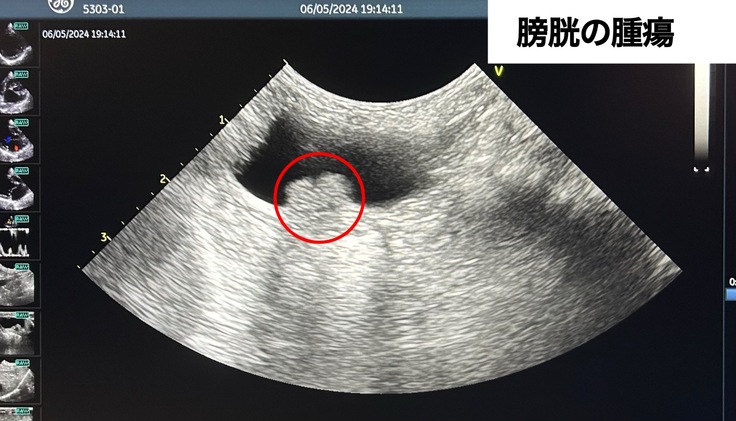

・膀胱に腫瘍があり今後も治療が必要なため